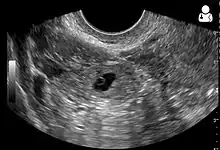

An ultrasound showing a gestational sac with fetal heart in the fallopian tube has a very high specificity of ectopic pregnancy. It involves a long, thin transducer, covered with the conducting gel and a plastic/latex sheath and inserted into the vagina.[32] Transvaginal ultrasonography has a sensitivity of at least 90% for ectopic pregnancy.[5] The diagnostic ultrasonographic finding in ectopic pregnancy is an adnexal mass that moves separately from the ovary. In around 60% of cases, it is an inhomogeneous or a noncystic adnexal mass sometimes known as the "blob sign". It is generally spherical, but a more tubular appearance may be seen in case of hematosalpinx. This sign has been estimated to have a sensitivity of 84% and specificity of 99% in diagnosing ectopic pregnancy.[5] In the study estimating these values, the blob sign had a positive predictive value of 96% and a negative predictive value of 95%.[5] The visualization of an empty extrauterine gestational sac is sometimes known as the "bagel sign", and is present in around 20% of cases.[5] In another 20% of cases, there is visualization of a gestational sac containing a yolk sac or an embryo.[5] Ectopic pregnancies where there is visualization of cardiac activity are sometimes termed "viable ectopic".[5]

Transvaginal ultrasonography of an ectopic pregnancy, showing the field of view in the following image

A "blob sign", which consists of the ectopic pregnancy. The ovary is distinguished from it by having follicles, whereof one is visible in the field. This patient had an intrauterine device (IUD) with progestogen, whose cross-section is visible in the field, leaving an ultrasound shadow distally to it.

Ultrasound image showing an ectopic pregnancy where a gestational sac and fetus has been formed